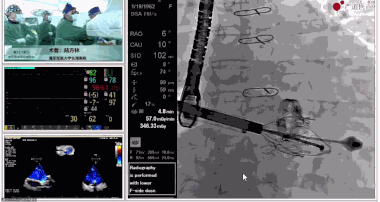

▲瓣膜植入過(guò)程

▲瓣膜植入后釋放的過(guò)程

在手術(shù)直播中瓣膜植入過(guò)程不到10分鐘,手術(shù)獲得圓滿(mǎn)成功,充分體現(xiàn)徐志云、陸方林團(tuán)隊(duì)技術(shù)精湛,團(tuán)隊(duì)協(xié)作默契及器械的優(yōu)越性。